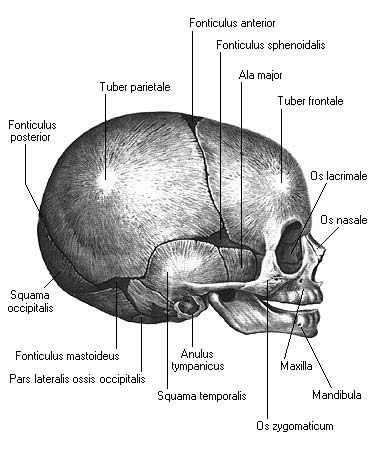

Анатомия детского черепа: Рентгеновские снимки и описание